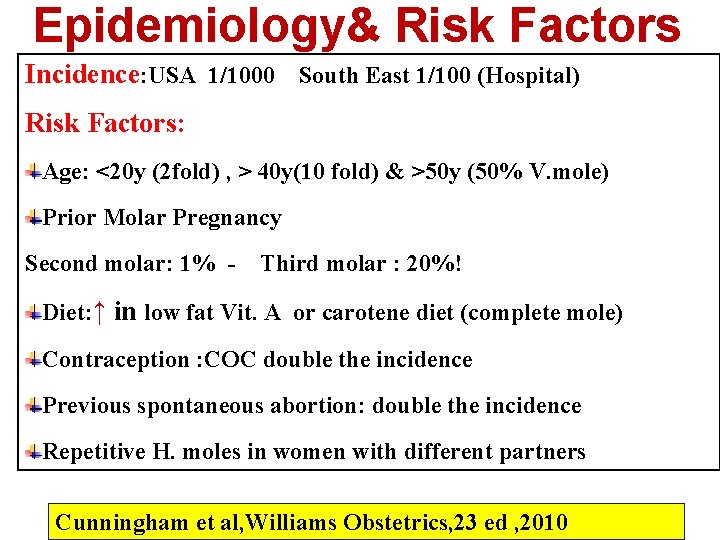

Epidemiology& Risk Factors Incidence: USA 1/1000 South East 1/100 (Hospital) Risk Factors: Age: <20 y (2 fold) , > 40 y(10 fold) & >50 y (50% V. mole) Prior Molar Pregnancy Second molar: 1% - Third molar : 20%! Diet: ↑ in low fat Vit. A or carotene diet (complete mole) Contraception : COC double the incidence Previous spontaneous abortion: double the incidence Repetitive H. moles in women with different partners Cunningham et al, Williams Obstetrics, 23 ed , 2010